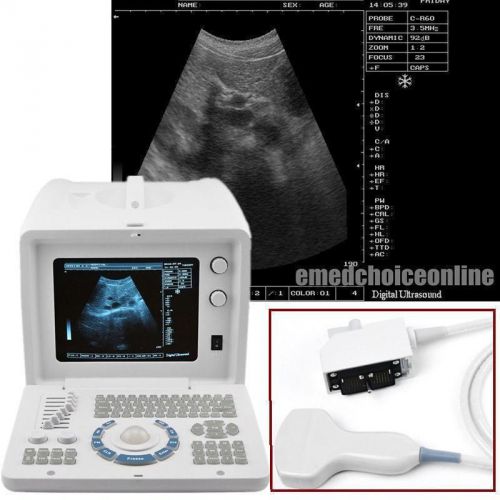

Brand | Ultrasound 9000E2 |

| MPN | Full Digital Ultrasound | ||

| Model | HIGH RESOLUTION | ||

Full Digital Portable laptop Ultrasound Scanner system CONVEX+LINEAR TWO PROBE

+New 3D Portable Digital Ultrasound Machine Scanner System with Linear Probe CE